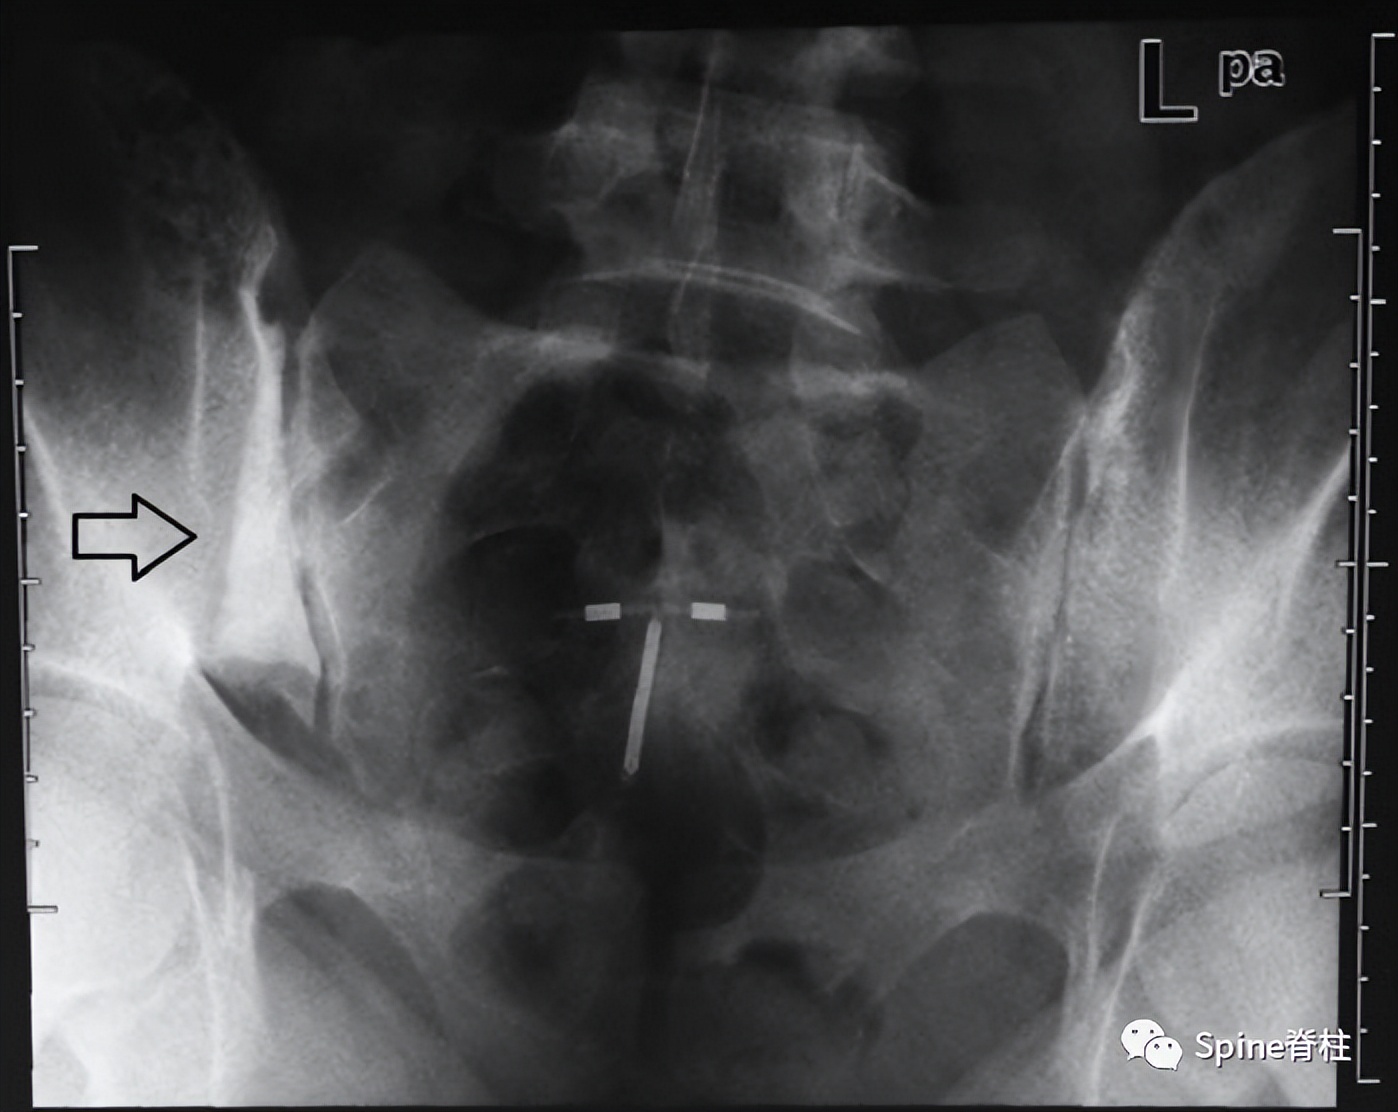

髂骨致密性骨炎通常是偶然诊断出来的。骶髂关节的髂侧表现出硬化,通常呈双侧、对称和三角形。硬化区轮廓分明且致密,主要位于关节的前中三分之一处。诊断主要依靠影像学上无骶骨受累和关节间隙变窄,但可能会出现骶骨附近对称性小局灶性硬化。此外,单侧髂骨致密性骨炎已有文献报道。

右侧髂骨单侧三角硬化(箭头) Mod Rheumatol (2012) 22:467–469